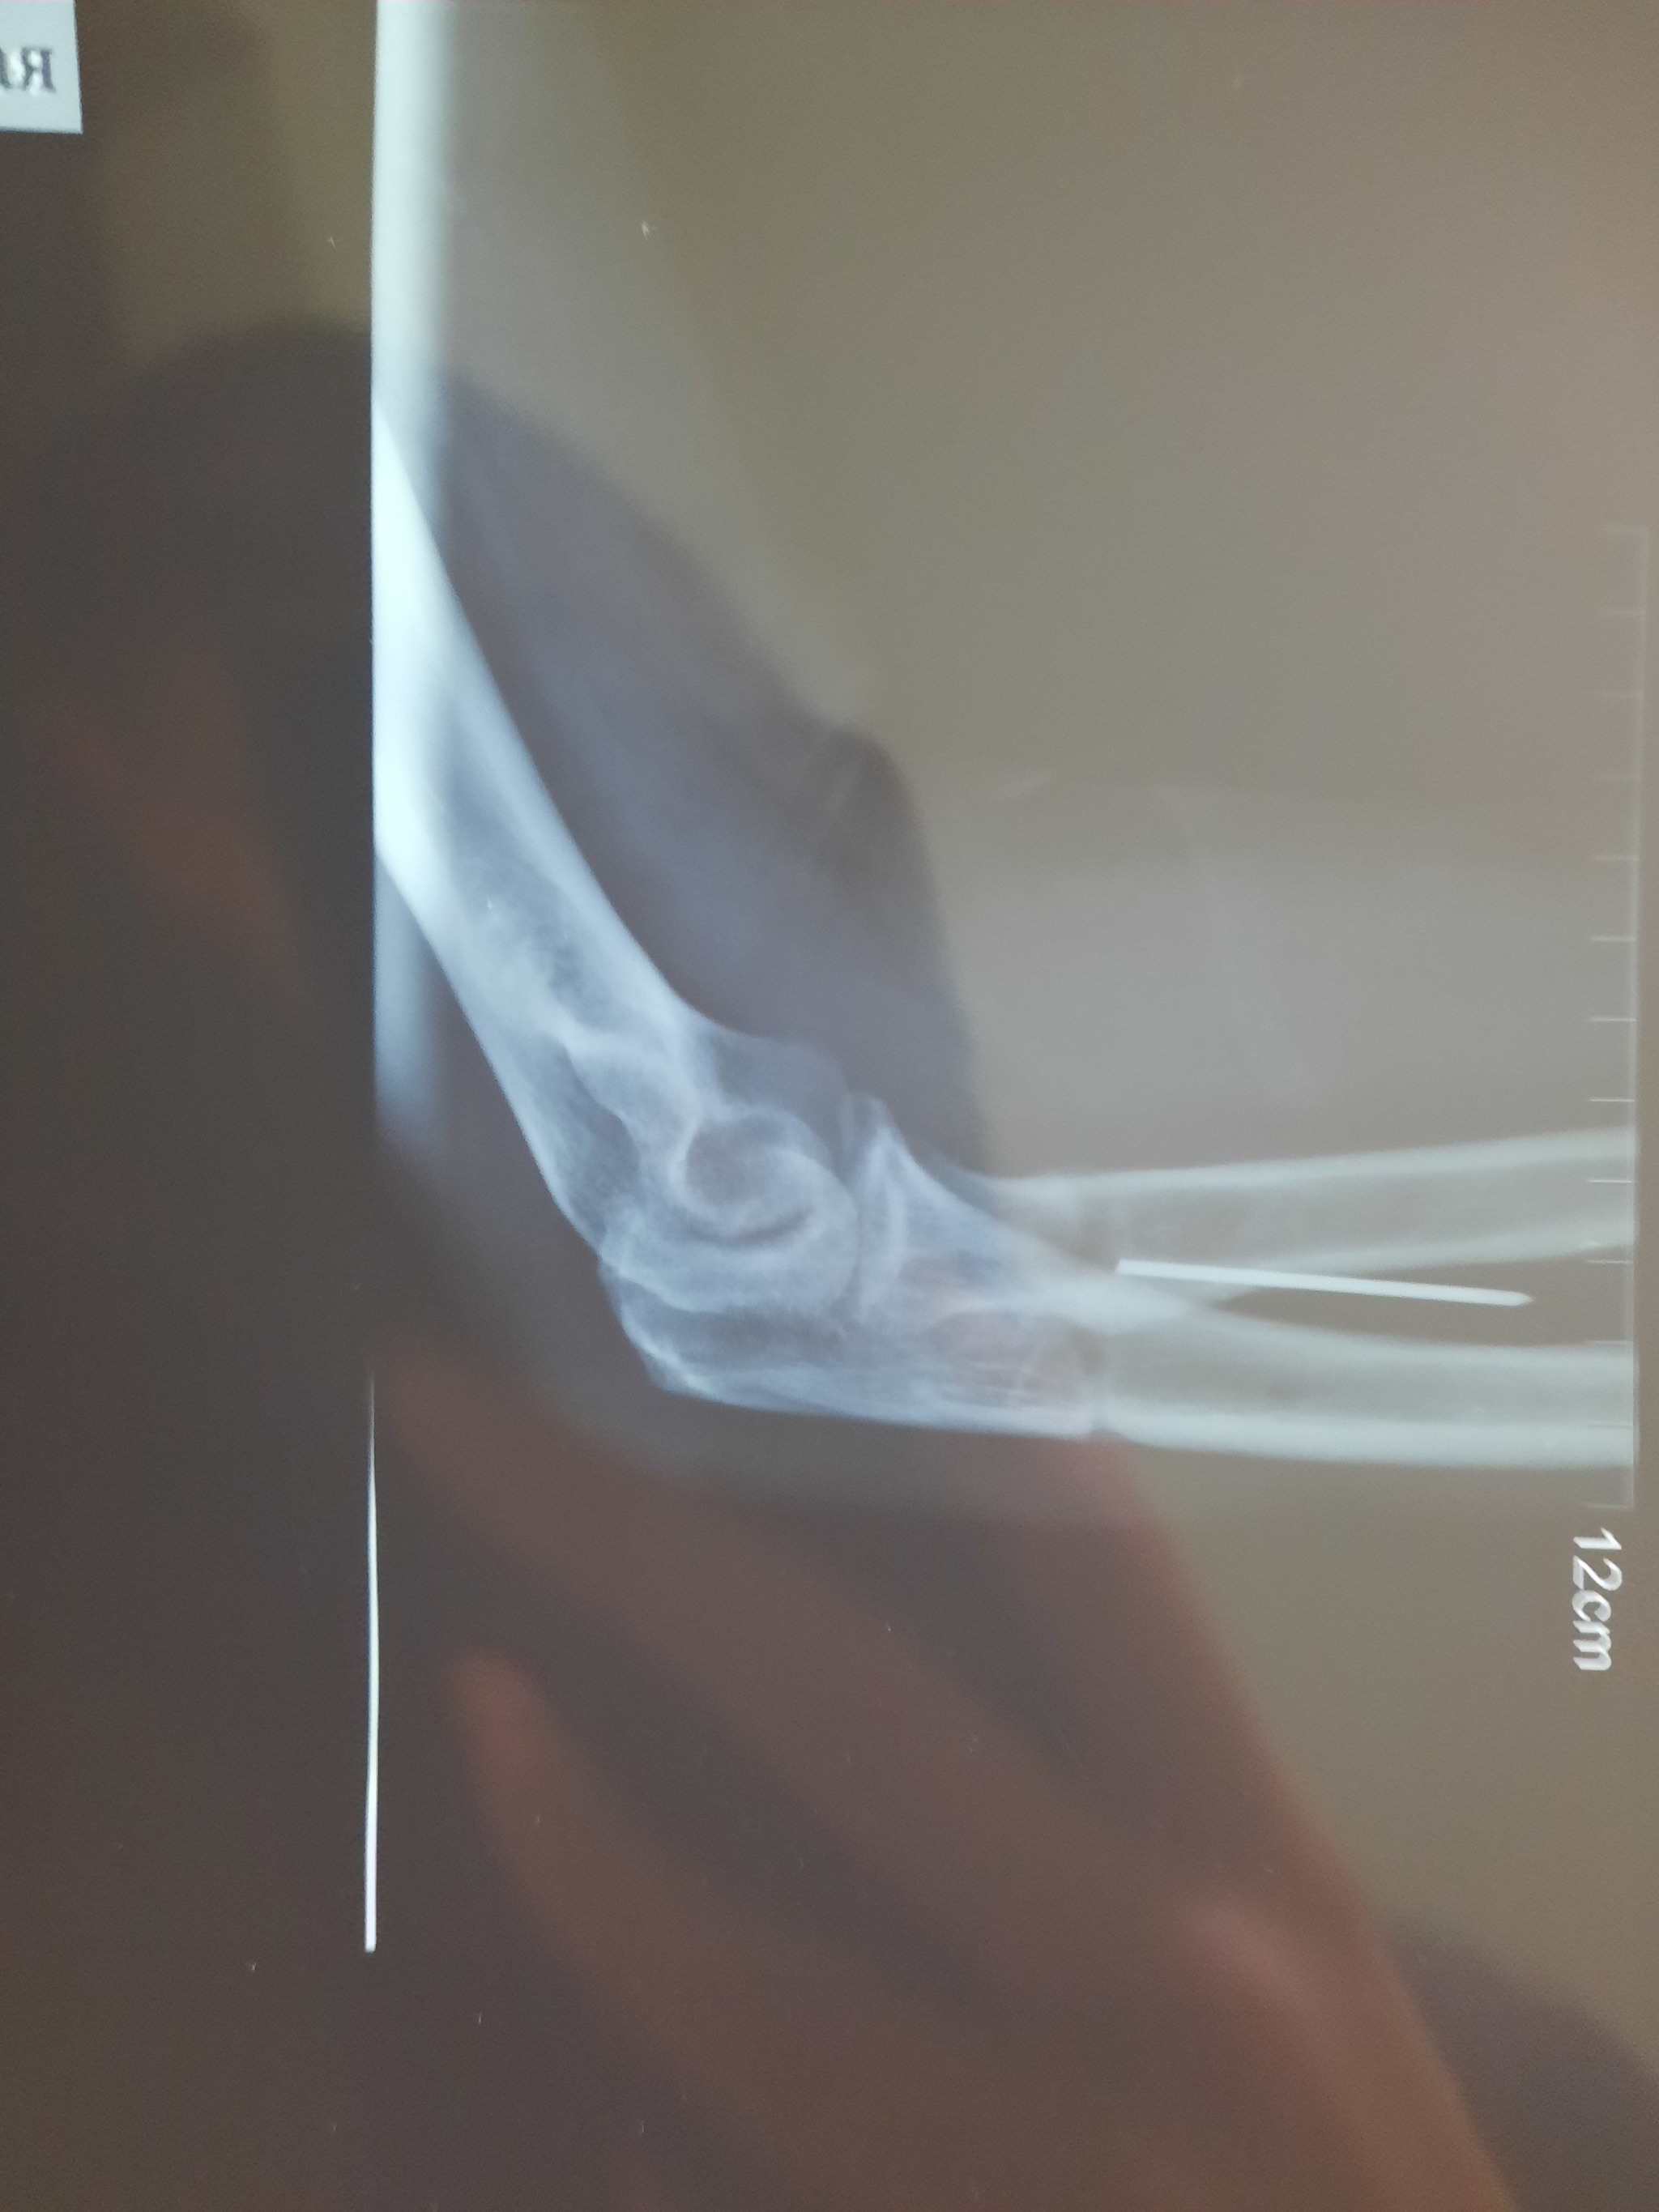

И вот три месяца назад стал жутко болеть этот палец, думаю видимо туфли неудобные купила. Но палец с каждым днем стал распухать просто жесть. Пришла я в травмпунк, мне доктор говорит "вы наверно стукнулись об угол мебели вот он и болит, ну ладно давайте я вам рентген сделаю". Я жду когда он мне результат скажет, а он выбегает злой и орёт на меня, мол "Вы почему врете то, иголку загнали в ногу и пришли как будто не знаете". Я в шоке, в голове каша, стало плохо и страшно. Столько лет иголка в ноге жила. Самое интересное что половина эта была с ушком, тобишь толстая половина иглы. Как она 16 лет сидела в ноге ума не приложу. И ведь не беспокоила ни разу. Сейчас от неё осталось напоминание в виде небольшого шва. Хируг сказал что повезло нереально как, игла была между костью и сухожилием, и воздух не попал, поэтому и не беспокоила. Вот такая история🤭